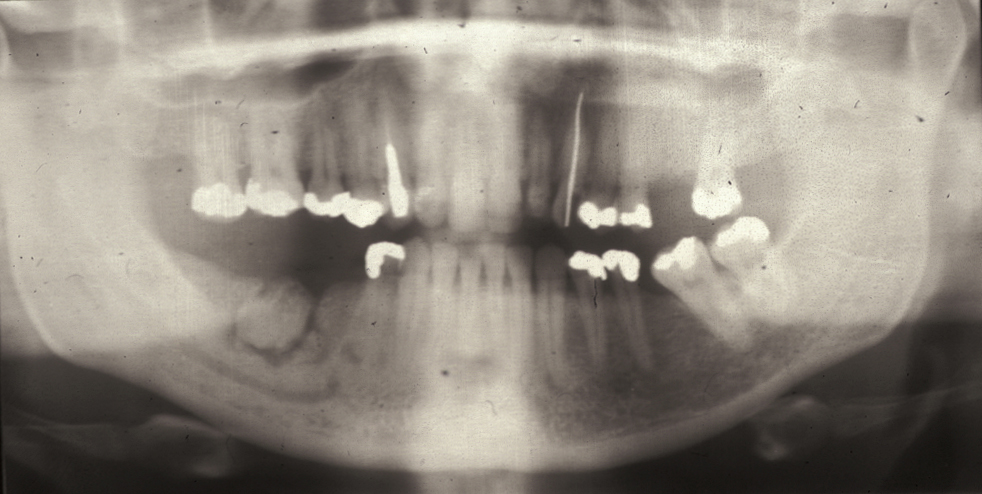

Follicular/plexiform ameloblastoma is a solid tumour, again found in the mandible. It is more aggressive in its clinical behaviour and resembles a solid tumour histologically (see Figure 5).

Figure 7: Sectional dental panoramic tomogram of the ‘soap bubble’ appearance of the solid variety of ameloblastoma.